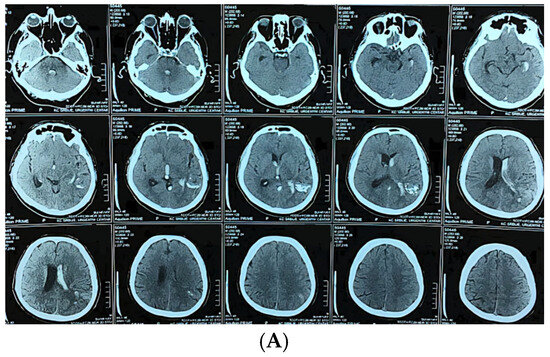

Functional and Hemodynamic Restoration After Microsurgical Resection of Compact High-Flow Temporo-Parieto-Occipital Arteriovenous Malformation

Background/Objectives: Arteriovenous malformations (AVMs) in the dominant temporo-parieto-occipital (TPO) junction of the brain are extremely rare and very difficult to remove surgically because this area includes multiple sensory and language networks. Due to the fact that many patients present with bleeding, surgeons [...] Read more.

Background/Objectives: Arteriovenous malformations (AVMs) in the dominant temporo-parieto-occipital (TPO) junction of the brain are extremely rare and very difficult to remove surgically because this area includes multiple sensory and language networks. Due to the fact that many patients present with bleeding, surgeons have to find a delicate balance between removing all of the AVM tissue and preserving the functional areas of the brain where important functions occur. This study is reporting a case demonstrating how precise clinical–radiologic correlation, detailed anatomical knowledge, and deliberate microsurgical techniques can allow safe removal of the AVM and improve the patient’s neurologic function without the need for additional intraoperative technology. Case Presentation: A 47-year-old right-handed male patient experienced persistent neurological deficits after experiencing a hemorrhage from an AVM in his dominant posterior hemisphere, which included mild language difficulties, right hemifacial–brachial spasticity, parietal sensory loss and a visual field defect of his right eye known as an inferior quadrantanopia localized to the TPO junction. Cerebral angiography identified a small, compact, high-flow AVM (40 × 30 mm) fed by distal branches of the middle cerebral artery (M4), posterior cerebral artery (P4), anterior cerebral artery (A4), as well as a small branch of the superior cerebellar artery (SCA). Blood drained into two veins of the Trolard and Labbé. The authors removed the AVM completely by circumferential dissection of the nidus along gliotic planes using a microscope. Feeders were then sequentially disconnected, and the venous outflow was preserved until the AVM could be removed en bloc. Post-operative angiograms demonstrated complete removal of the AVM with normalization of blood flow to the surrounding cortex. The patient’s neurologic function improved over time and at three months post-operatively, he was functioning independently (modified Rankin Scale = 1; Barthel Index = 100) and there was no evidence of residual nidus or edema on imaging. Conclusions: High-flow AVMs in the dominant TPO junction can be completely removed using a disciplined microsurgical approach and a feeder first/vein last disconnection method based on anatomy. The patient’s improvement in function represented reperfusion and reintegration of an injured but still functional network of the brain, reinforcing the idea that careful observation, a deep understanding of brain anatomy, and restrained surgical technique are critical to achieving long-term results in AVM surgery. Full article